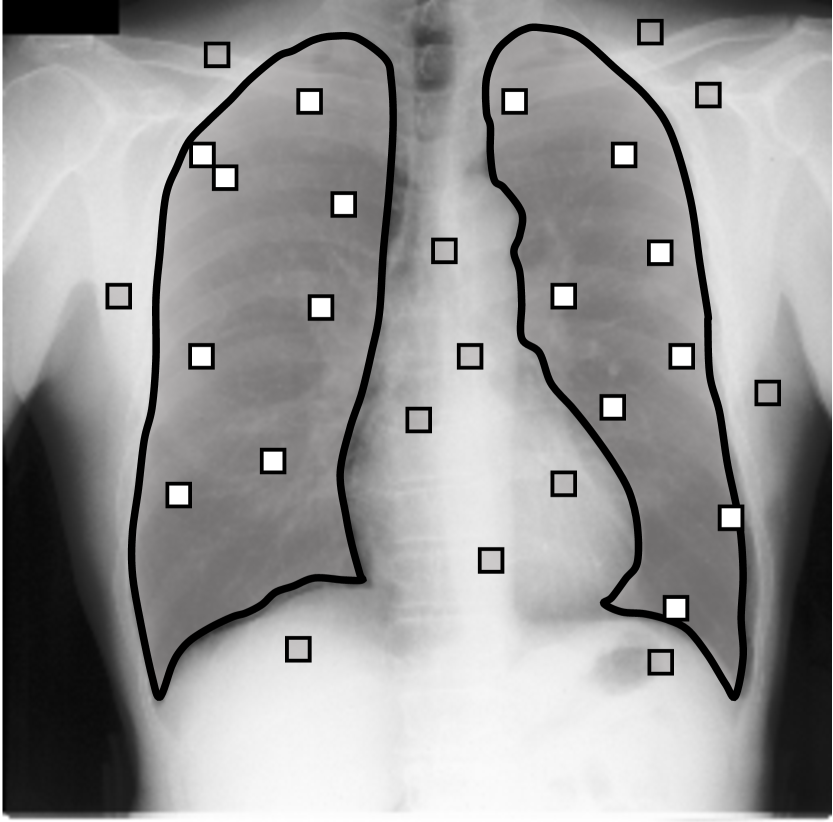

Network predictions can be over confident if bias shows up in training labels. Some works (Zhang et al., 2020b; Li et al., 2021) choose to trust the network prediction probability to correct label noises, i.e. they believe predictions with small confidence is likely to be wrong while pixels with large confidence tend to be correctly predicted. However, the network can fit to noisy labels quickly and be overconfident when trained with biased noisy labels. This phenomenon is also observed by Zhang et al. (2016). In Figure A.3(a), we train a network with dilated noises and show its prediction probability map, i.e. the output after sigmoid. The red pixel is predicted as foreground with a high probability , whereas it is actually in background. Therefore, methods based on trusting the network predictions cannot correct this label because the network is over confident. And since the network can fit to noise rapidly, early learning techniques also cannot eliminate this bias. Our method works because we do not trust the network prediction. Instead, we compare it to the clean label in validation set and estimate the bias. We then eliminate this bias in the training prediction. We also show how the prediction probability changes while training the model in Figure A.3(b). It shows that the model can be over confident quickly while training. So methods that employ early learning techniques (Liu et al., 2020; Arpit et al., 2017; Liu et al., 2022) are hard to work under biased noisy labels.

Noisy annotations with random inner holes. Our Markov noise model assumes the spatial bias occurs around the true boundary, but it does not reject other random noises like inner holes. Figure A.4 shows an expanded noise with low-frequency inner holes (1st row), and our method can correct this hole after 2 iterations.